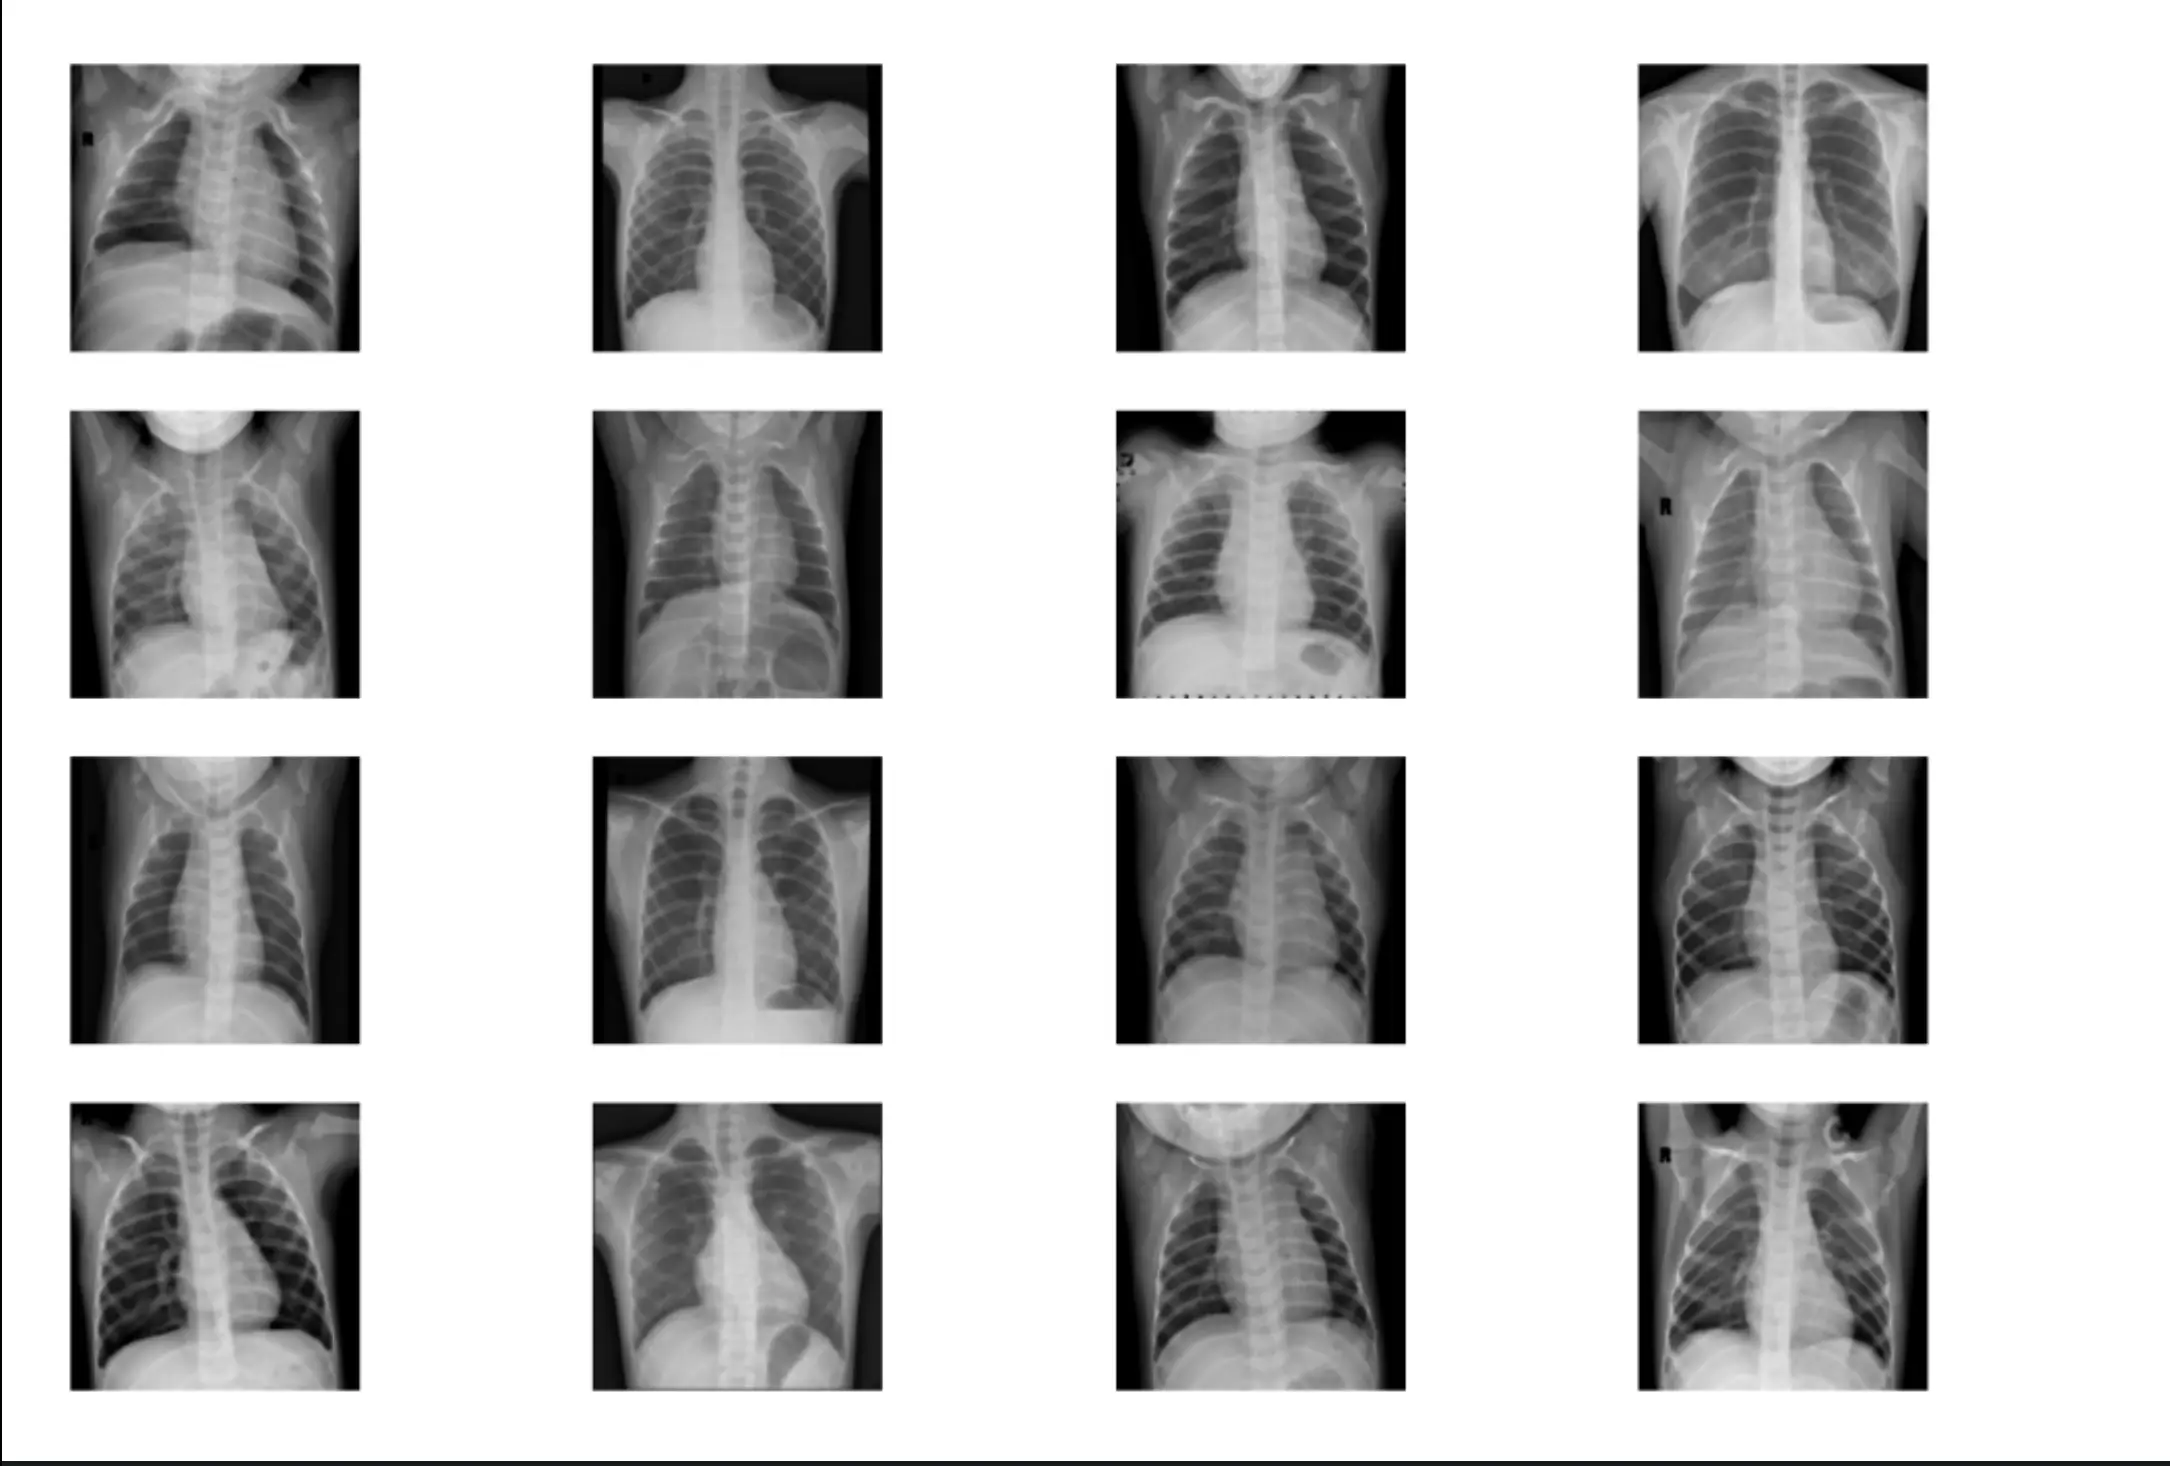

A deep learning comparative study using Simple NN, CNN, and Residual CNN architectures to classify chest X-rays as Normal or Pneumonia with TensorFlow and Keras.